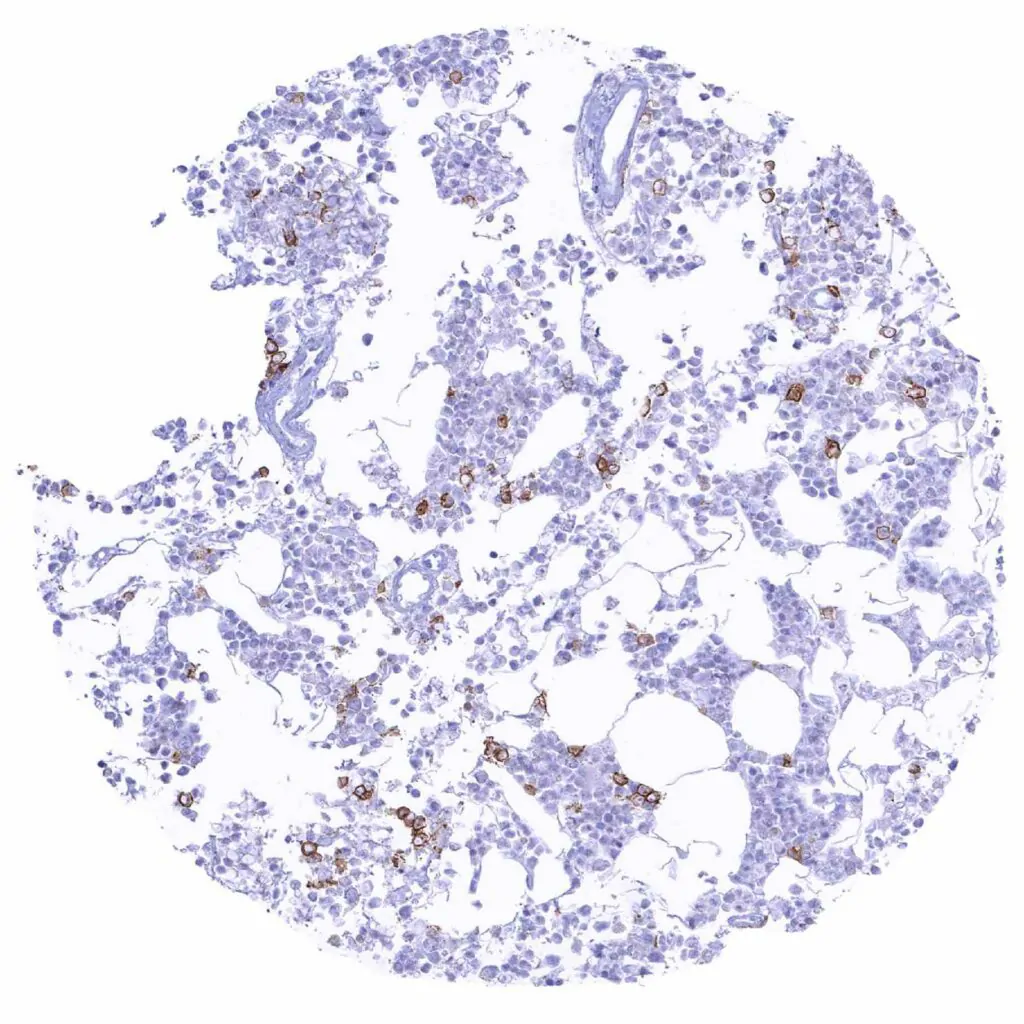

Lymph node – Distinct CD38 staining of a subset of lympho–monocytic cells.

Lymph node – Distinct CD38 staining of a subset of lympho–monocytic cells